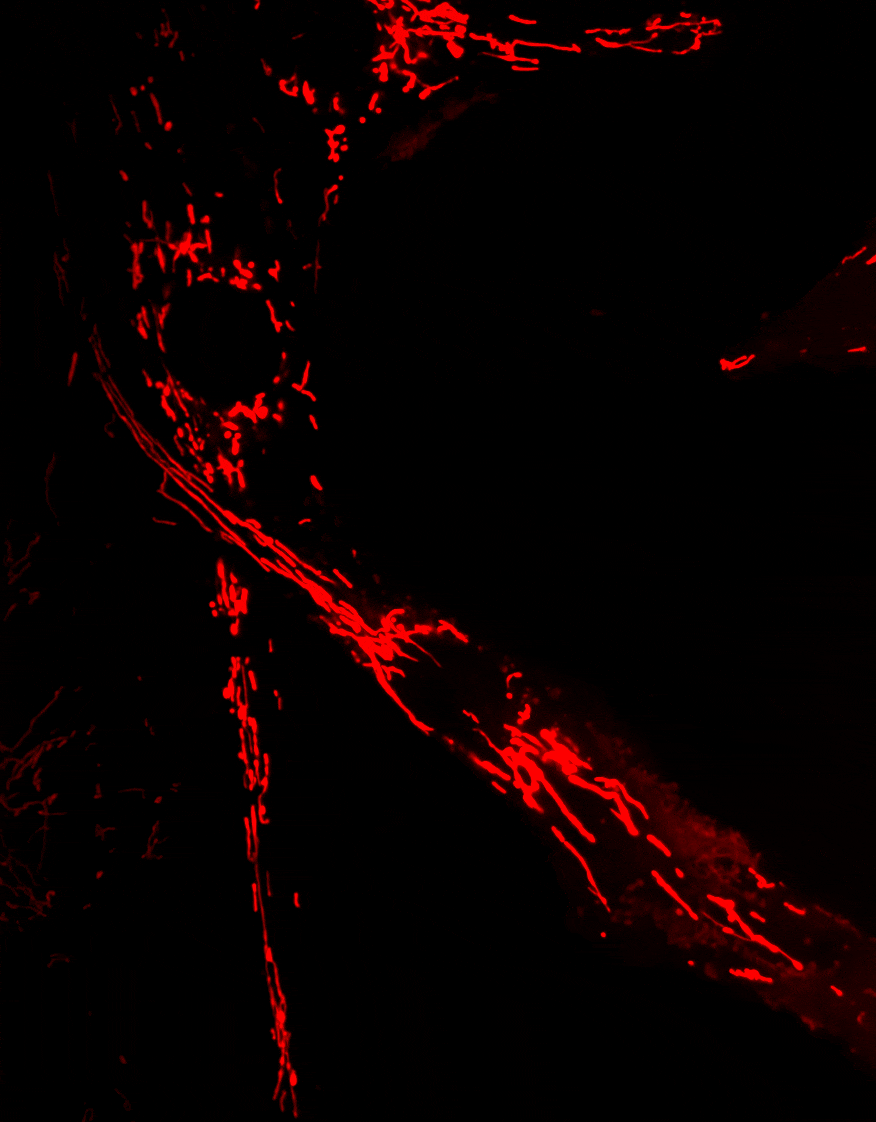

Mitophagy, the process responsible for the removal of damaged mitochondria, is disrupted in several neurodegenerative diseases. Mutations in the Optn gene have been linked to disorders such as glaucoma and amyotrophic lateral sclerosis (ALS).

We investigate the role of OPTN in mitochondrial transport and clearance, and examine how defects of these biological processes may contribute to the onset and progression of neurodegenerative diseases.

Phosphorylation of Optineurin by protein kinase D regulates Parkin-dependent mitophagy. Weil R, Laplantine E, Attailia M, Oudin A, Curic S, Yokota A, Banide E, Génin P. iScience. 2024 Nov 13;27(12):111384. doi: 10.1016/j.isci.2024.111384. eCollection 2024 Dec 20. PMID: 39669425